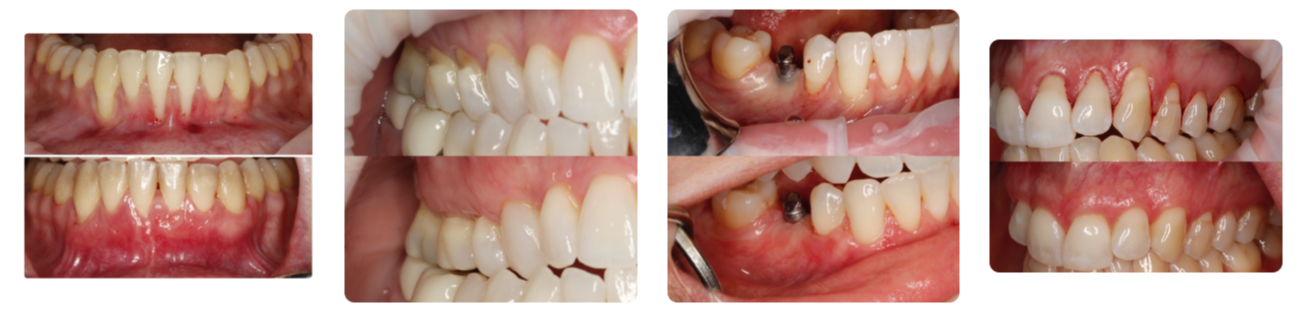

Management of Periodontal Disease and Mucogingival Defects: Implementing an Efficient Periodontal Program into Your General Dentistry Practice!

- Non-surgical and surgical periodontal therapy and decide what treatment to offer based on your diagnosis.

- Soft Tissue Technique Selection and Workflow Algorithm.

- Diagnose utilizing the new periodontal classification system

- Establish with confidence the diagnose and management of soft tissue problems around teeth and dental implants